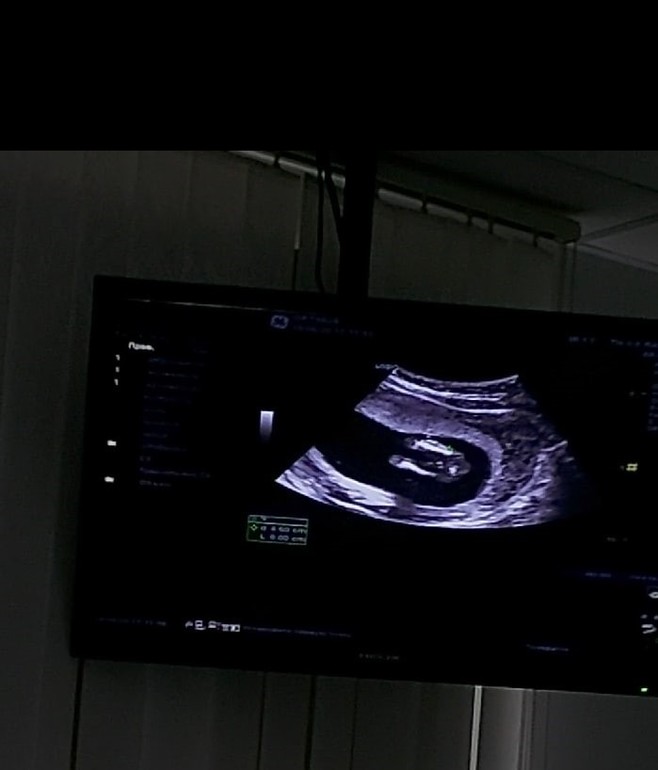

узи в 17 недель. Сказали пол ребенка!

Пол малышаВчера была на узи, сказали пол нашего ребеночка. У нас тадааам ДЕВОЧКА! Даже как-то не верится, на узи такая кааааак девочка?! И глаза квадратные😆 Всегда казалось что после двух девочек обязательно должен получиться пацан🤣

На узи переспросила несколько раз, точно девочка??? Мне развернули датчик и показали что между ножек пирожок😁 Вот честно, в упор смотрю и не вижу где там пирожок😆 Фото ниже для самых глазастых, а вы видите тут пирожок?😄